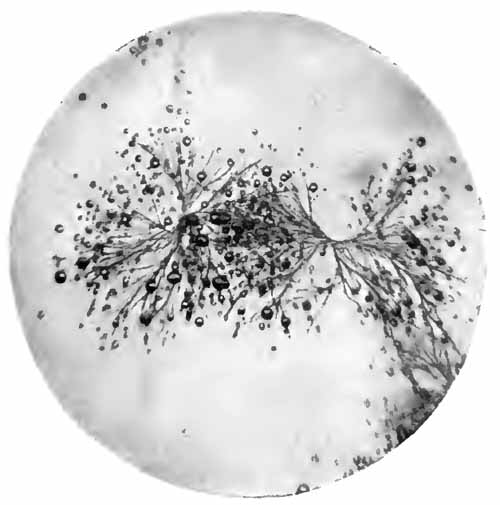

Sputum from a case of actinomycosis

FIG. 8.—Sputum from a case of actinomycosis; stained (Jakob).

5. Actinomyces Bovis (Ray-fungus).—In the sputum of pulmonary actinomycosis and in the pus from actinomycotic lesions elsewhere small, yellowish, "sulphur" granules can be detected with the unaided eye. The fungus can be seen by crushing one of these granules between slide and cover, and examining with a low power. It consists of a network of threads having a more or less radial arrangement, those at the periphery presenting club-shaped extremities (Fig. 8). This organism, also called Streptothrix actinomyces, apparently stands midway between the bacteria and the molds. It stains by Gram's method.

[p. 32] Actinomycosis of the lung is rare. The clinical picture is that of tuberculosis.